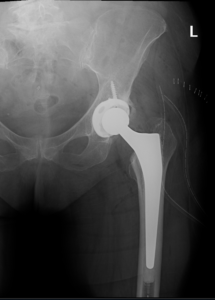

The surgery is performed under general anesthesia. During the procedure a surgical cut is made over the hip to expose the hip joint and the femur is dislocated from the acetabulum. The surface of the socket is cleaned and the damaged or arthritic bone is removed using a reamer. The acetabular component is inserted into the socket using screws or occasionally bone cement. A liner made of plastic, ceramic or metal is placed inside the acetabular component. The femur or thigh bone is then prepared by removing the arthritic bone using special instruments, to exactly fit the new metal femoral component. The femoral component is then inserted to the femur either by a press fit or using bone cement. Then the femoral head component made of metal or ceramic is placed on the femoral stem. All the new parts are secured in place using special cement. The muscles and tendons around the new joint are repaired and the incision is closed.

Total hip replacement (THR) is a surgical procedure in which the damaged cartilage and bone is removed from the hip joint and replaced with artificial components. The hip joint is one of the body’s largest weight-bearing joints, located between the thigh bone (femur) and the pelvis (acetabulum). It is a ball and socket joint in which the head of the femur is the ball and the pelvic acetabulum forms the socket. The joint surface is covered by smooth articular cartilage which acts as a cushion and enables smooth movements of the joint.

Surgical Procedure

Surgery may be recommended, if conservative treatment options such as anti-inflammatory medications and physical therapy do not relieve the symptoms.